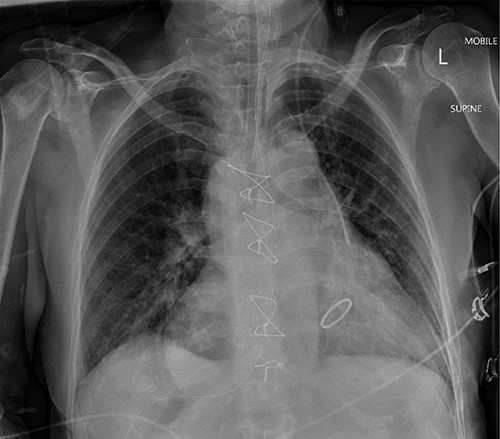

Figure 1 shows the plain film chest X-ray. Commuted tomography (CT) with intravenous contrast of the abdomen and pelvis confirmed SI totalis (Fig. 2). Polysplenia with five splenunculi, a lobulated 130 mm mass with heterogenous contrast enhancement and free fluid were noted in the right upper quadrant on CT (Fig. 2). Upon return from CT the patient became tachycardiac and hypotensive to 62/44 mmHg for which she was fluid responsive to 2 L IV crystalloid. Repeat haemoglobin was now 109 with a lactate of 0.9 and no significant acid–base disturbance. Group and Save, IV 10 mg vitamin K and 2300 IU of prothrombinex-VF were ordered, and the general surgical team was consulted urgently.

Mobile anteroposterior chest film. Demonstrates the nasogastric tube right of midline in stomach and the left internal jugular central line left of midline in the superior vena cava.